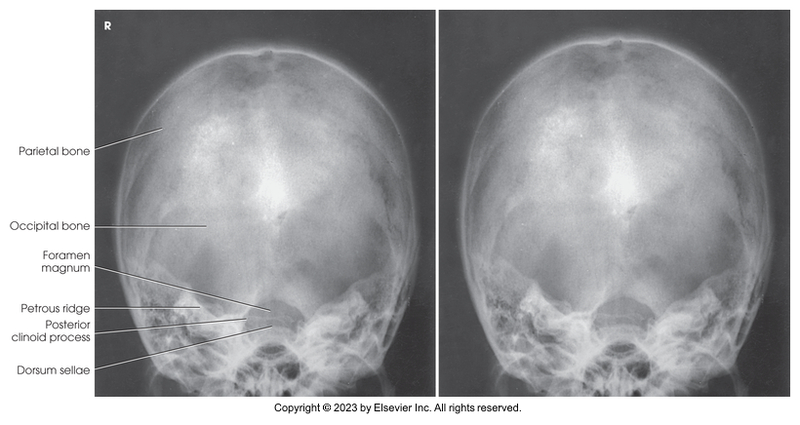

AP axial of skull - Towne method

AP axial skull - Towne method